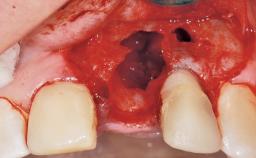

This 43-year-old male patient, a non-smoker, came to our practice because of a fracture of tooth 12 caused by a bicycle accident. Due to the combined para- and infrabony crown and root fracture, tooth extraction, and subsequent implant placement were suggested to the patient as the therapy of choice. The patient had high esthetic expectations with regard to the treatment outcome and asked for an immediate fixed provisional restoration. His individual esthetic risk profile summed up to a medium esthetic risk.

Placement Protocol Immediate implant placement

Socket Morphology Single-root socket

Socket Integrity Sufficient, with intact bone walls